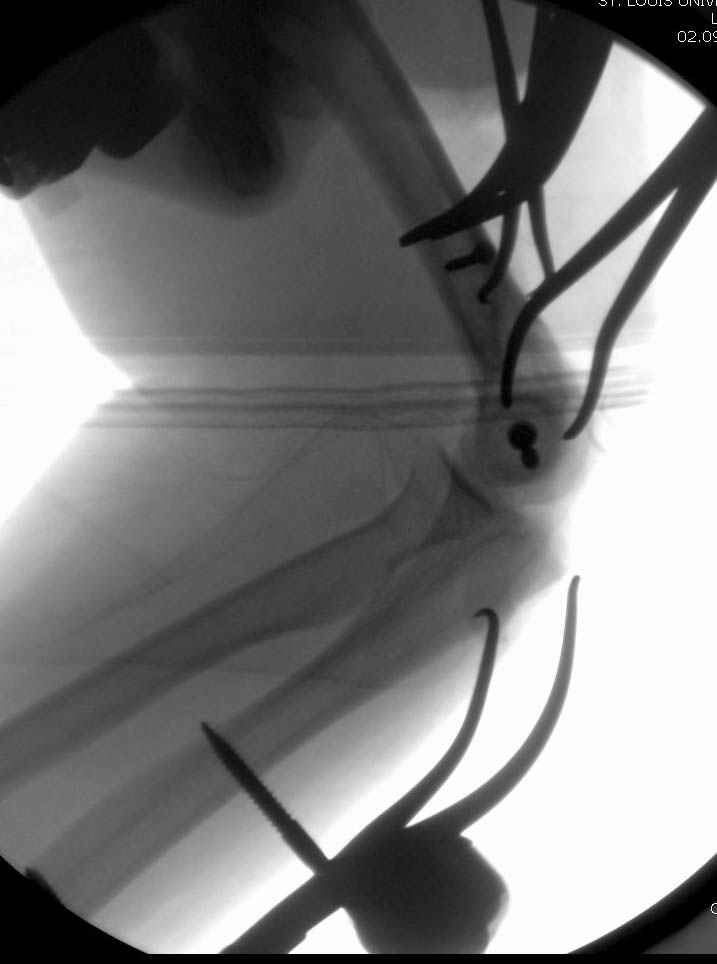

Примерный случай, только перелом был открытый, в задне-медиальной стороне рана около 2 см по характеру "изнутри кнаружи", неврологический статус со слабостью сгибания мизинца, также слабая абдукция и аддукция указательного пальца и сгибания в кисти.

Больному сделали обработку и наложили временный аппарат внешной фиксации плечо-предплечье.

На шестой день сделали открытую репозицию чрезлоктевым доступом двумя locking plate, локтевой нерв был ушибленным, после операции положительная динамика в Flexor Carpi Ulnaris. Фиксацию локтевого отростка произвели tension band technique с дополнительным шурупом.

Этапы операции на снимках....